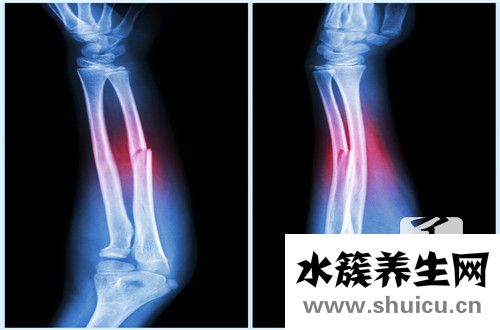

骨骼對人體非常重要。如果缺鈣,很可能會出現骨骼缺陷,甚至影響人體的身高和骨密度。骨的正常代謝功能可以促進細胞的生成。眾所周知,紅細胞是造血干細胞,因此骨代謝也間接地在人體血液的正常運轉中發...